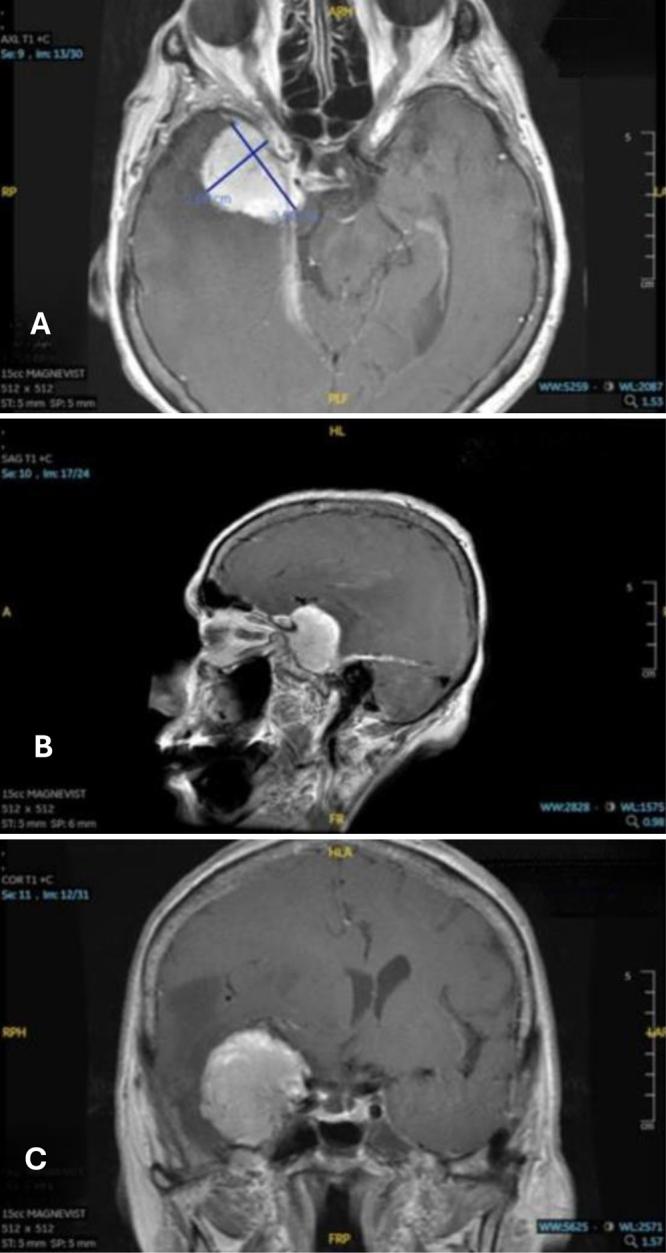

Decades after exposure each patient developed distinct brain tumors, a WHO grade I meningioma and a SMARCB1-deficient sinonasal carcinoma. Following craniotomies for resection and adjuvant therapy, only 1 patient's tumor progressed. Literature revealed radiation exposure analogous for these tumor's etiologies and identified various Chernobyl exposure groups parallel to these patients like cleanup workers, evacuees, and residents of highly contaminated areas and their descendants.

暴露数十年后,每位患者都患上了不同的脑肿瘤,一例是世界卫生组织一级脑膜瘤,另一例是SMARCB1缺陷型鼻窦癌。在进行开颅手术切除和辅助治疗后,只有1例患者的肿瘤进展。文献显示这些肿瘤病因的辐射暴露情况类似,并确定了与这些患者类似的切尔诺贝利暴露群体,如清理工人、撤离人员、高污染地区居民及其后代。